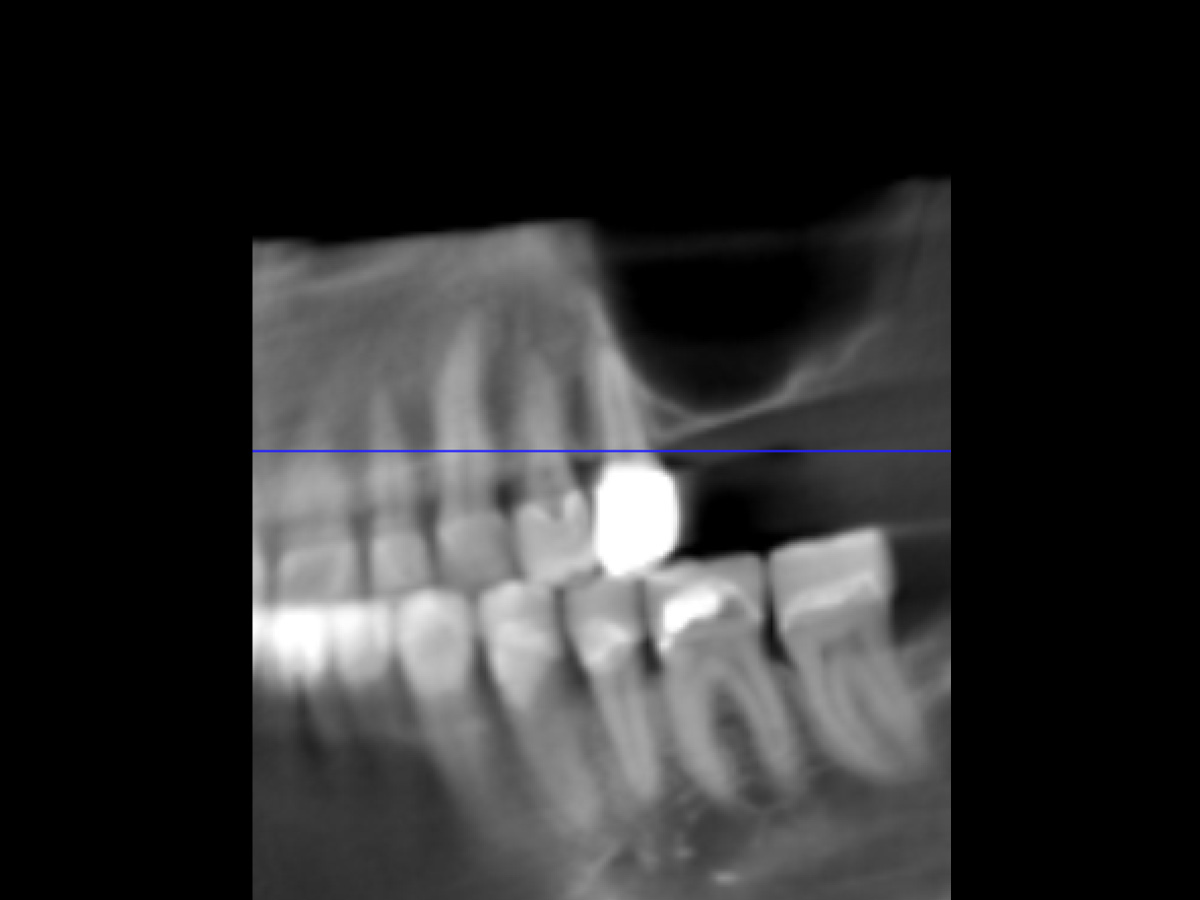

Abbildung 1

OPG Ausgangsbild (Ausschnitt).